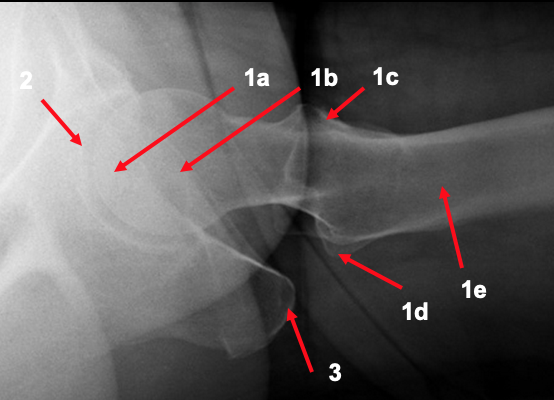

What is shown by the arrows on the lateral hip radiograph?

1. femur

a. head

b. neck

c. greater trochanter

d. lesser trochanter

e. proximal shaft

2. acetabulum

3. ischial tuberosity